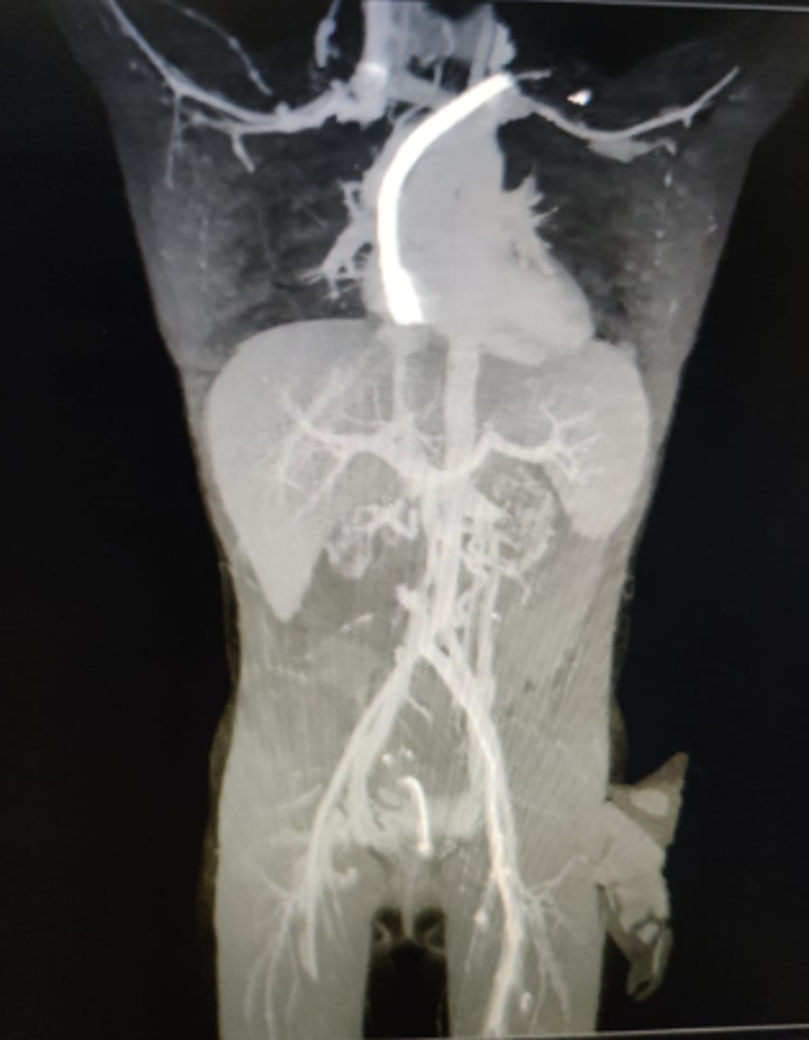

DSA (digital subtraction angiography) study was suggestive of chronic thrombosis of Infra-renal IVC (Inferior Vena Cava) extending to the right external iliac vein, likely related to the tunneled dialysis catheter. Her immunological workup was negative for any Donor Specific Antibodies. She was planned for a kidney transplant with her mother as the donor. Graft Kidney was implanted intraperitoneally onto the left common iliac vessels followed by bladder augmentation and a continent urinary diversion. Her post-operative course was uneventful with an adequate functioning allograft. She was discharged with a serum creatinine of 0.3 mg/dl on post-operative day 9. She is maintaining a good urine output of 2.5-3 liters through the diversion stoma at 3 weeks.